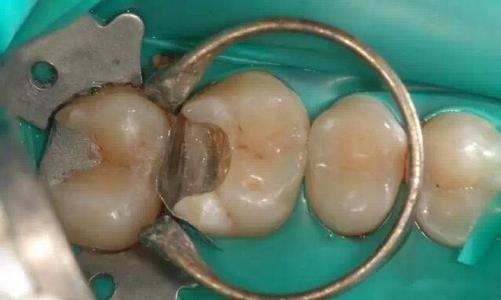

深圳補牙多數用美國進口3M納米樹脂材料,價格在280-480元之間,分為3M Z250(適合前牙)、3M P60和3M Z350(前後牙都適合)。烤瓷牙相對比較便宜,但是美觀度比較差,而全瓷牙比較貴,美觀自然,更受患者喜愛。全瓷牙相對又分為很多不同品牌,例如德國威蘭德、美國LAVA、國產愛爾創、德國澤康等,具體補牙和全瓷牙價目表可以參考維港口腔收費標準。